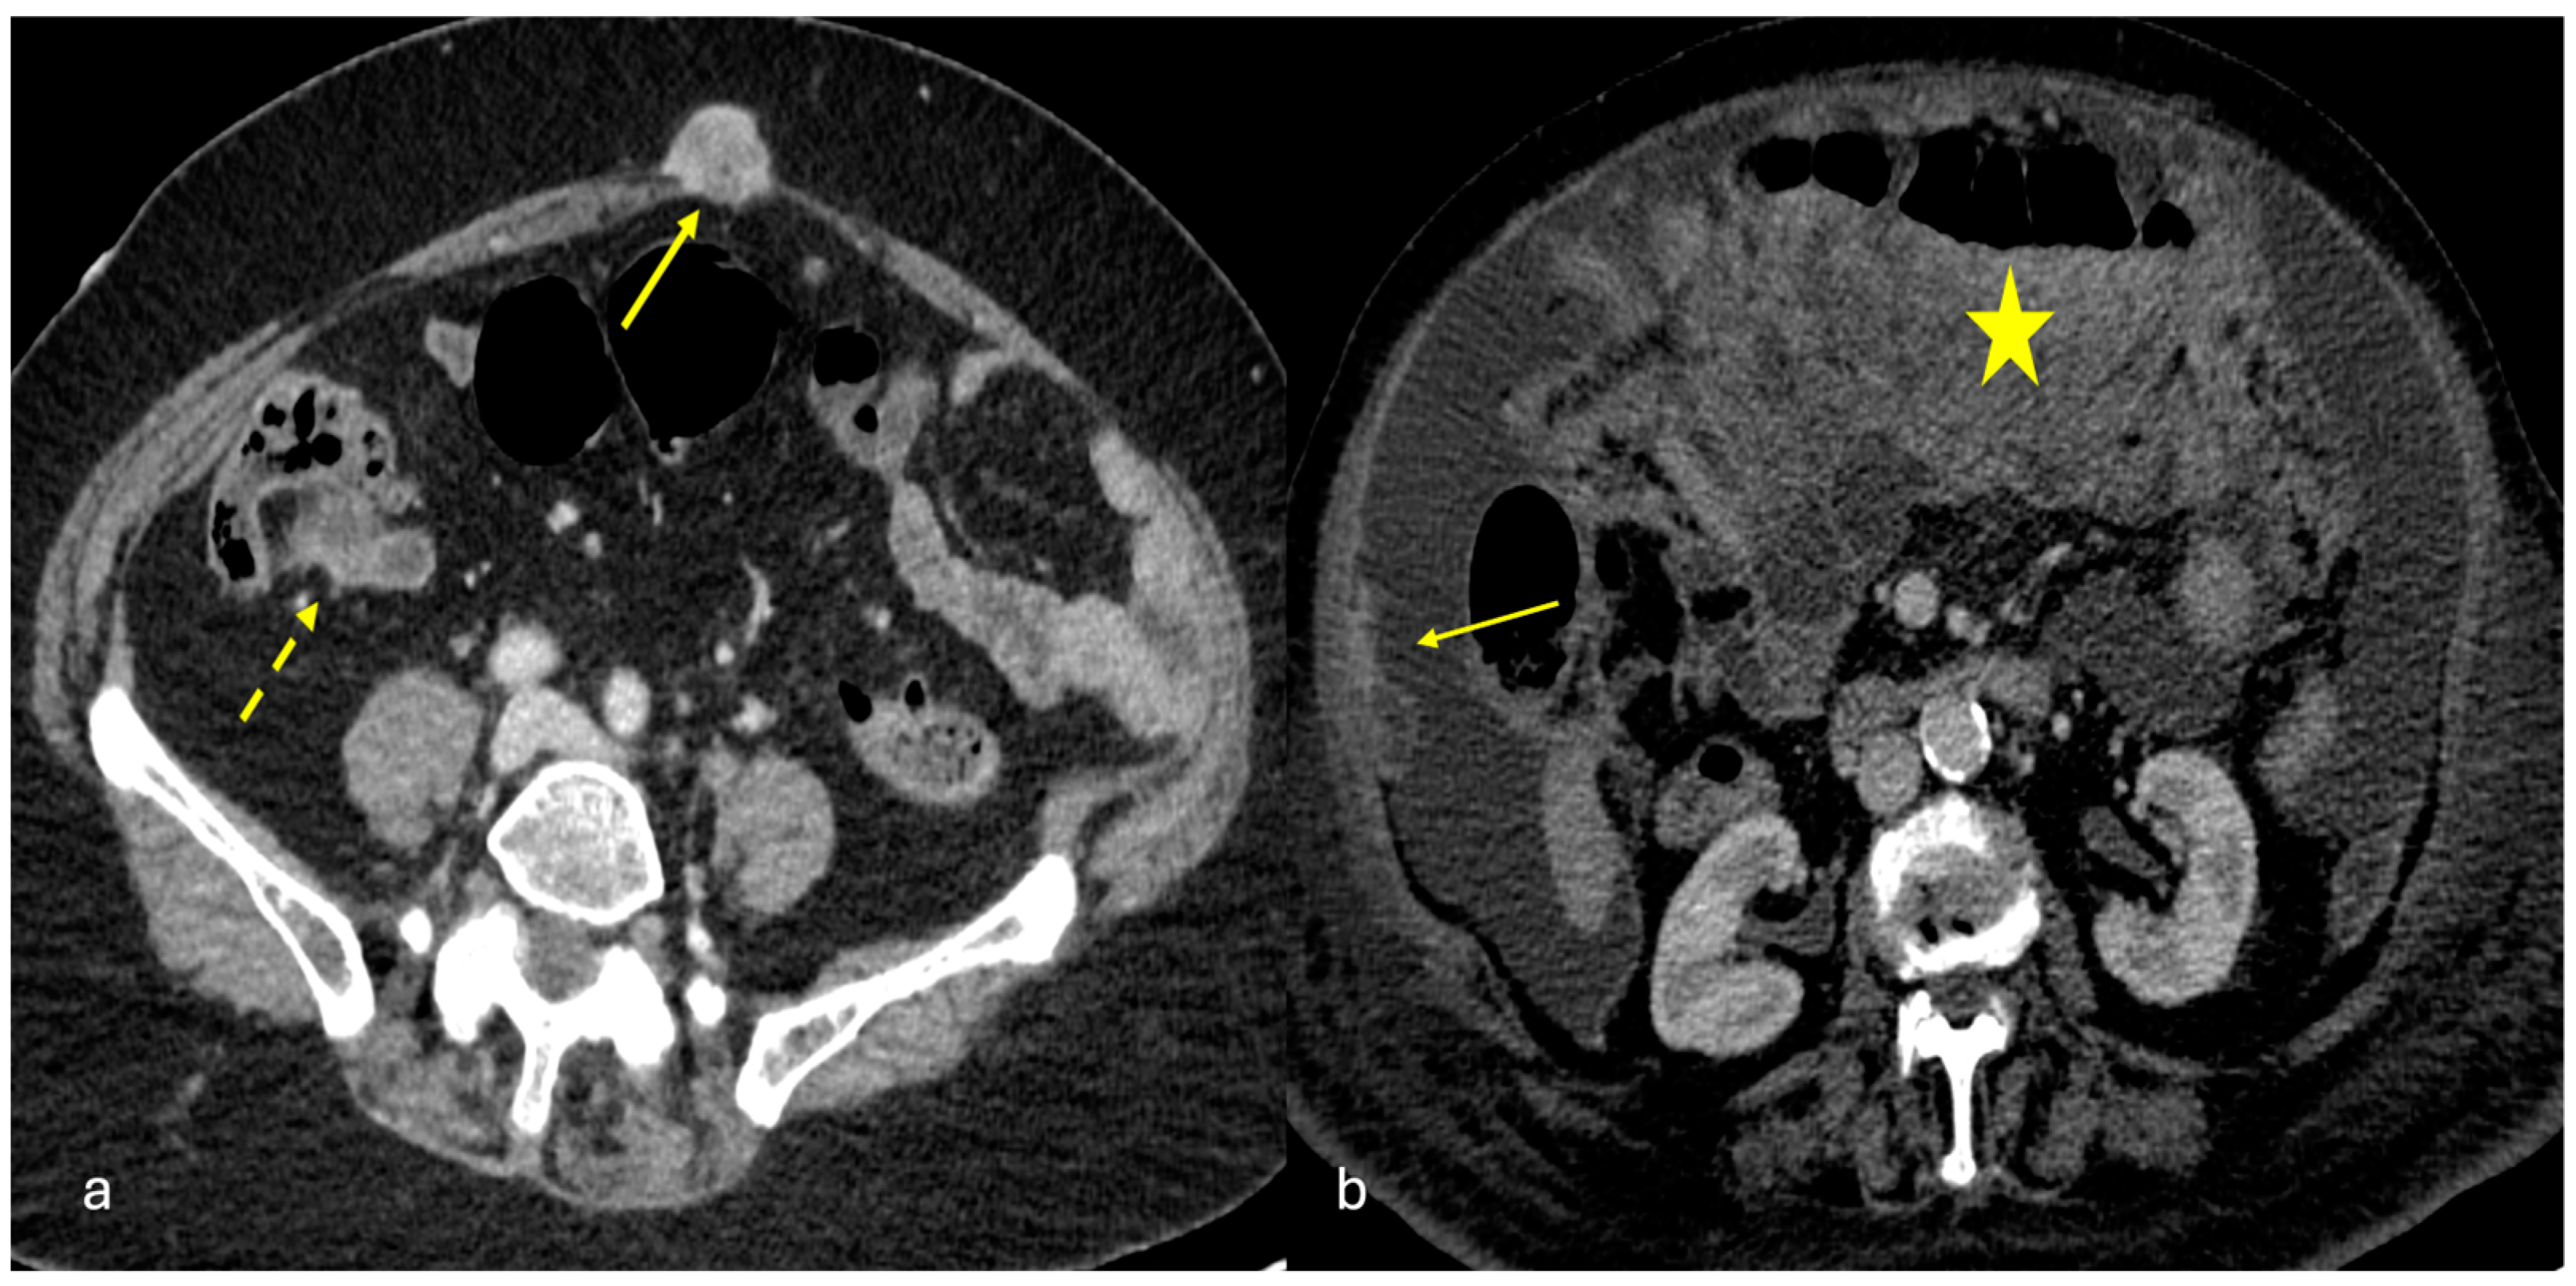

3.4.1. Post-Traumatic Mesenteric Injuries

3.4.3. Splenosis